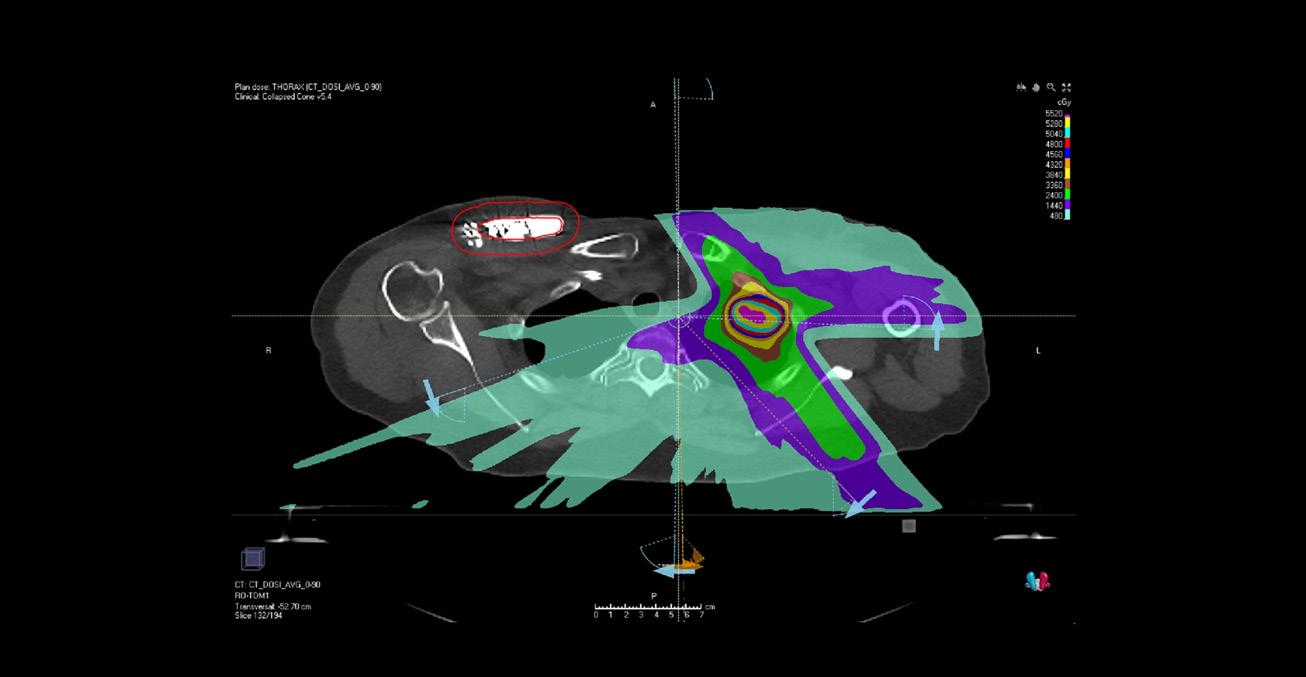

Dans un premier temps, il s’agit d’aligner le patient en recalant les clichés orthogonaux avec les images de projection reconstruites du rachis (figure 3).

Puis le positionnement est réalisé sur la sonde DAI : les manipulateurs créent le modèle de corrélation entre celle-ci et les repères externes. Pour cela, une série d’images radiographiques est réalisée à différents moments du cycle respiratoire. On peut alors situer la cible dans l’espace, à chaque instant du cycle respiratoire.

Le modèle respiratoire acquis, le début du traitement est validé par l’onco-radiothérapeute. Le bras robotisé se déplace autour du patient pour la réalisation des faisceaux de traitement. La surveillance est continue pendant ces étapes de placement et de traitement, par les caméras, interphone et scope. Le chariot d’urgence, ainsi qu’un défibrillateur manuel sont disponibles au poste de traitement.

Une fois le traitement terminé, le DAI est de nouveau réglé, puis le transfert du patient au CHRU est réalisé (si besoin accompagné du cardiologue) où il reste quelques jours à quelques semaines sous surveillance en Unité de soins intensifs cardiologiques puis en hospitalisation traditionnelle cardiologique. Un suivi à domicile est ensuite réalisé en télé cardiologie, permettant d’identifier la survenue de nouveaux troubles du rythme, même à distance du traitement.

Résultats

Douze patients ont été inclus entre avril 2020 et mai 2021. Trois sont encore dans la période de blanking, qui correspond au premier mois après la séance de radiothérapie, durée durant laquelle le traitement n’a pas délivré toute sa potentialité. L’ensemble des patients prévus a pu bénéficier de cette technique. « Une réduction majeure des évènements rythmiques a été observée, en passant d’une médiane de 25 [17-61] évènements observés dans l’année précédant la radiothérapie à aucun [0-1], après un suivi médian post-radiothérapie de 5,2 mois »5. Deux décès ont été observés dans les semaines qui ont suivi le traitement. Cependant, une bonne tolérance, sans effet indésirable, est pour le moment constatée.

Discussion – Perspectives

Actuellement, il n’existe que 3 études de recherches cliniques portant sur cette thématique, toutes 3 monocentriques et n’ayant inclus au total que 39 patients6,7,8.Il reste donc de nombreux points à développer afin de confirmer ces résultats très préliminaires en termes d’efficacité et de sécurité. Les mécanismes d’action des rayonnements ionisants, au niveau cardiaque, restent à découvrir, en particulier dans le cadre d’un traitement délivré en une seule séance.

Figure

Toutefois, ce type de prise en charge montre d’intéressantes perspectives dans les applications de traitements stéréotaxiques, et ce au-delà de celles concernant les localisations tumorales. La radiochirurgie permet également d’établir des ponts entre différentes spécialités et ainsi de bénéficier de l’expertise d’équipes jusqu’alors très spécialisées.

Enfin, les techniques utilisées peuvent encore connaitre des améliorations majeures. Ainsi, l’émergence actuelle de l’IRM dans le champ de la radiothérapie pourrait permettre d’envisager une simplification de la détermination des volumes cibles (en cas d’utilisation d’IRM de centrage) et une simplification des méthodes de tracking (en cas d’utilisation d’une IRM-linac, accélérateur linéaire avec dispositif IRM embarqué).

REMERCIEMENTS